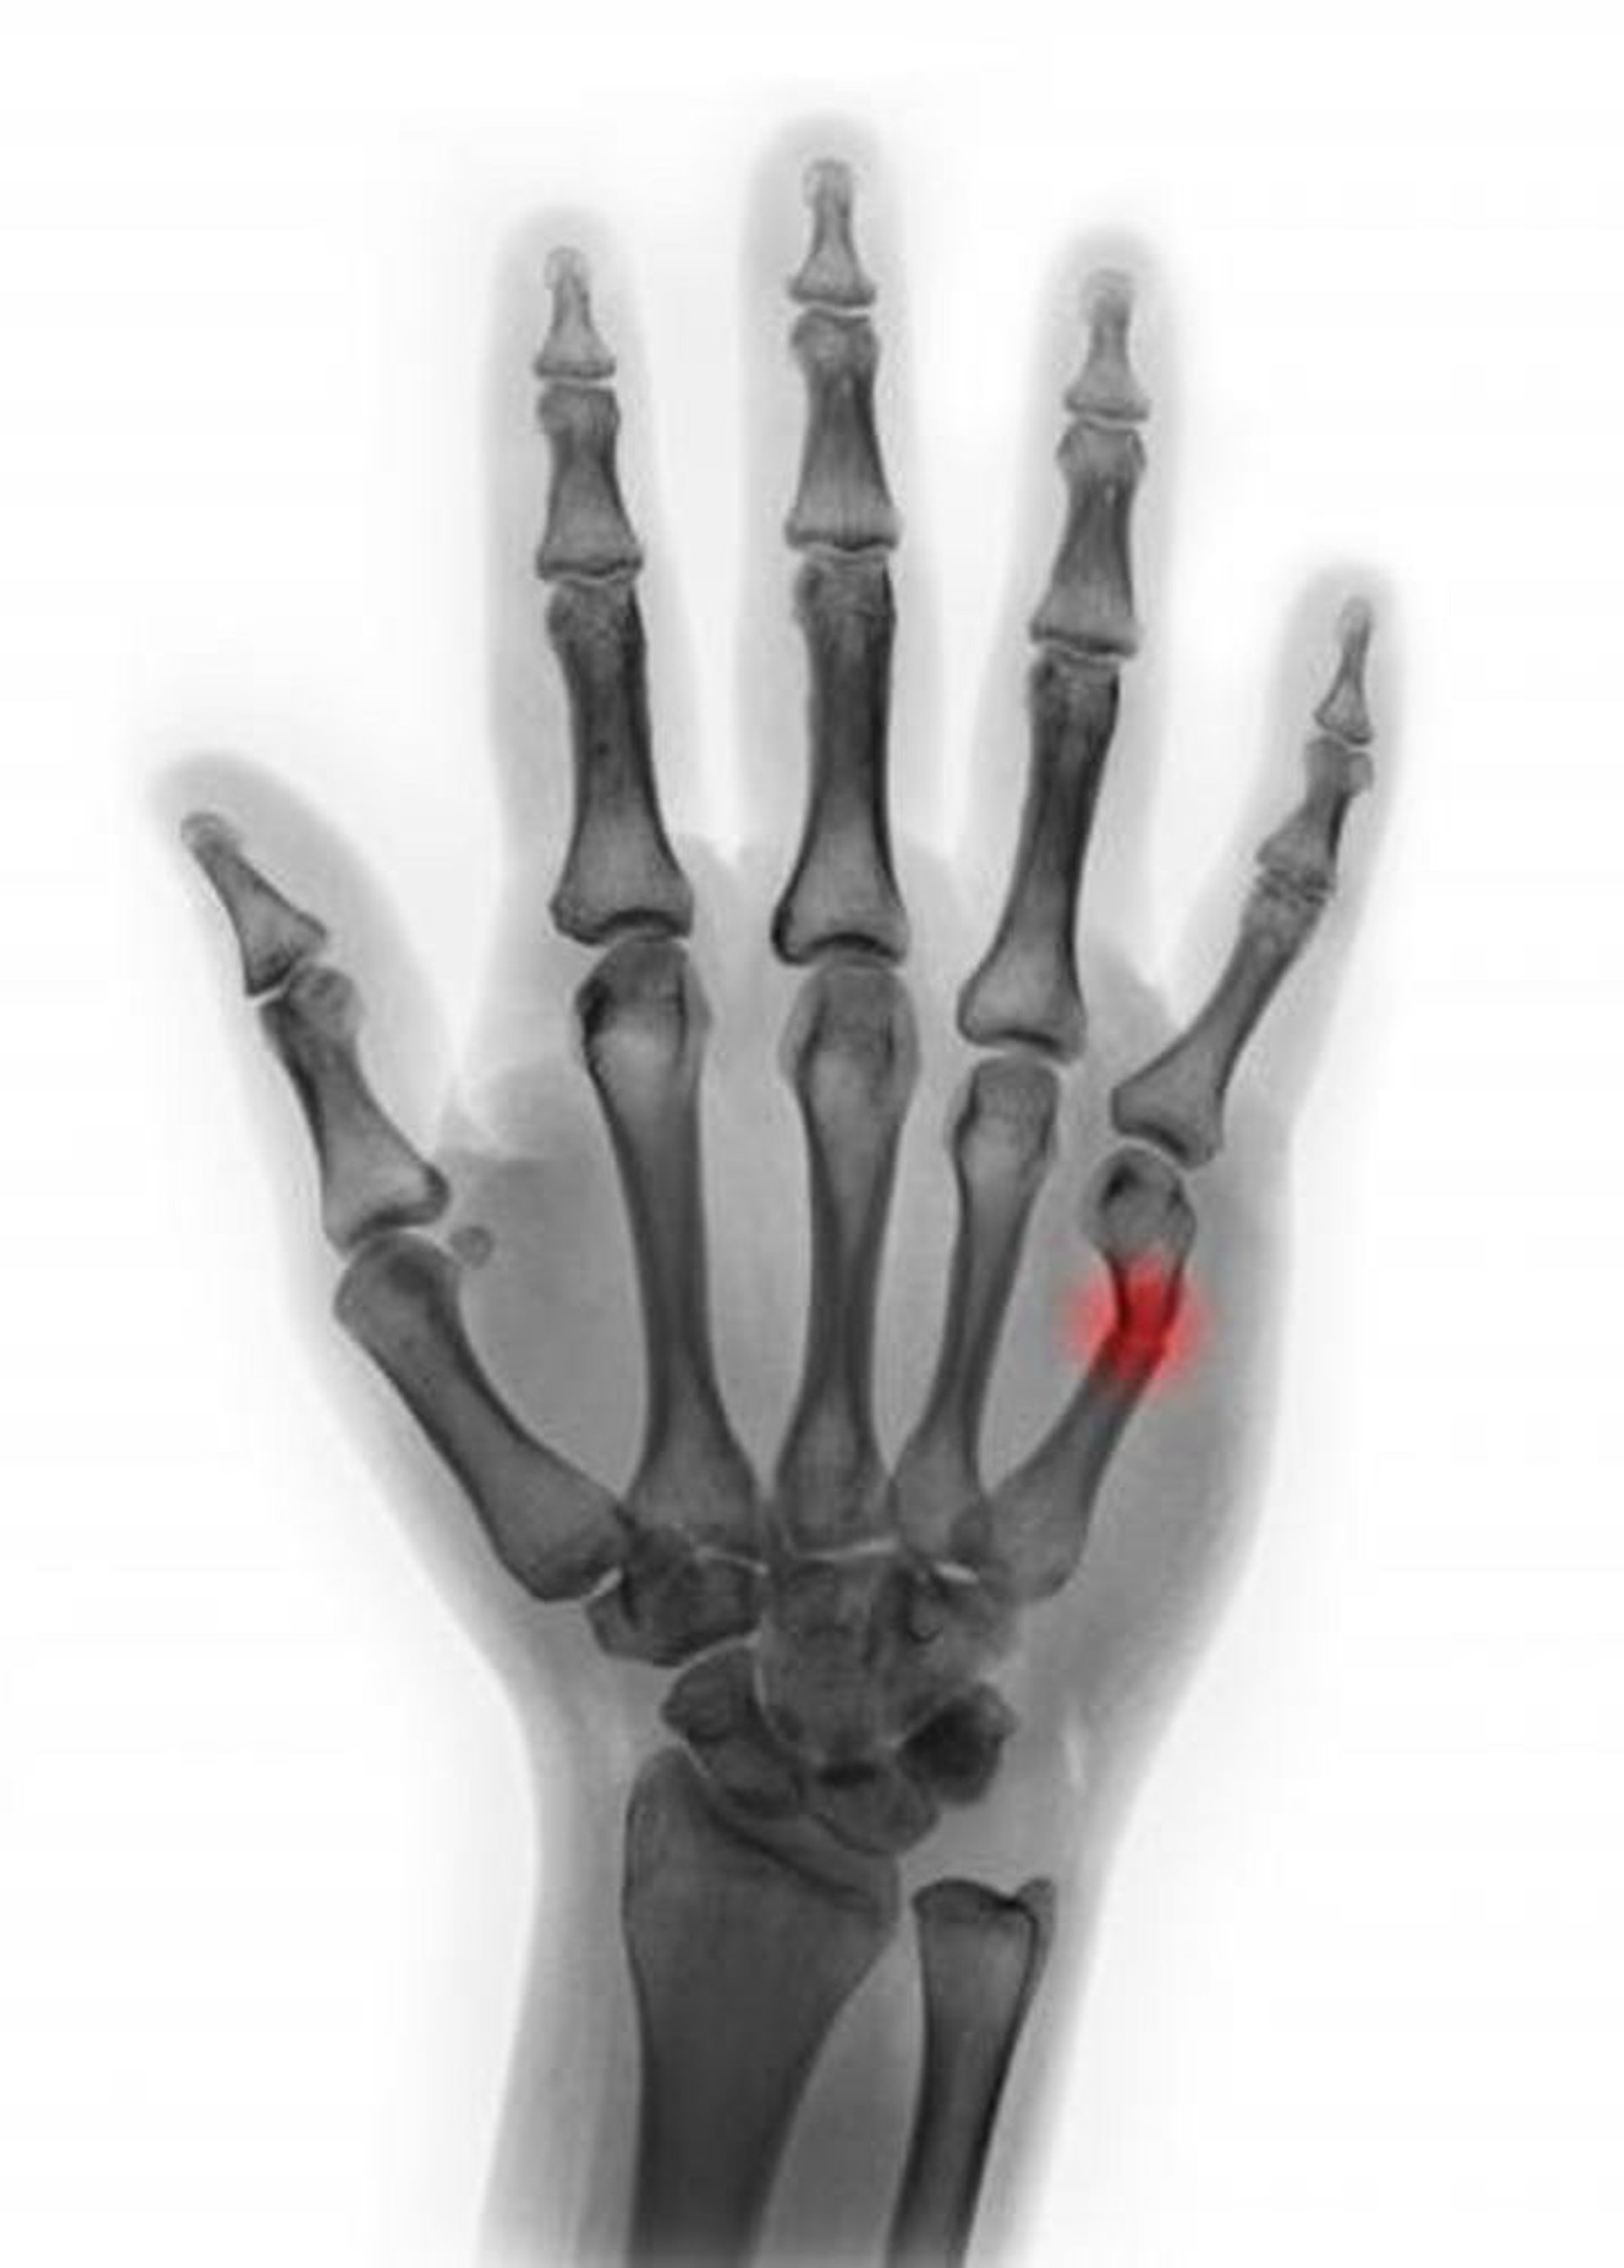

Frattura del 5o collo metacarpale

Questa radiografia colorata mostra una frattura del collo del 5° metacarpo. In questa prospettiva, l'angolazione sembra essere < 45°, suggerendo che la riduzione non sia necessaria.

SCOTT CAMAZINE/SCIENCE PHOTO LIBRARY